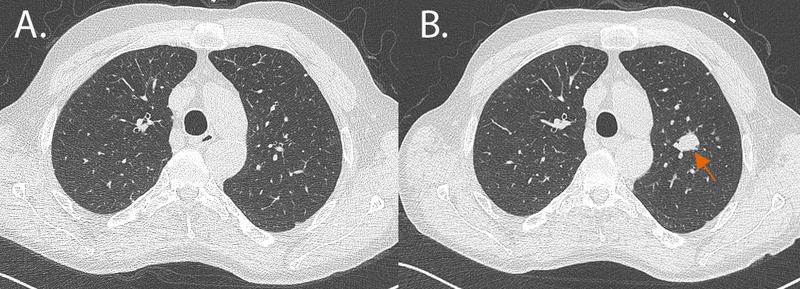

Früherkennung bei Lungenkrebs: Screening, aber richtig!

Krebsfrüherkennungsprogramme existieren im deutschen Gesundheitswesen unter anderem für den Brustkrebs, den Gebärmutterhalskrebs und den Darmkrebs. In den…